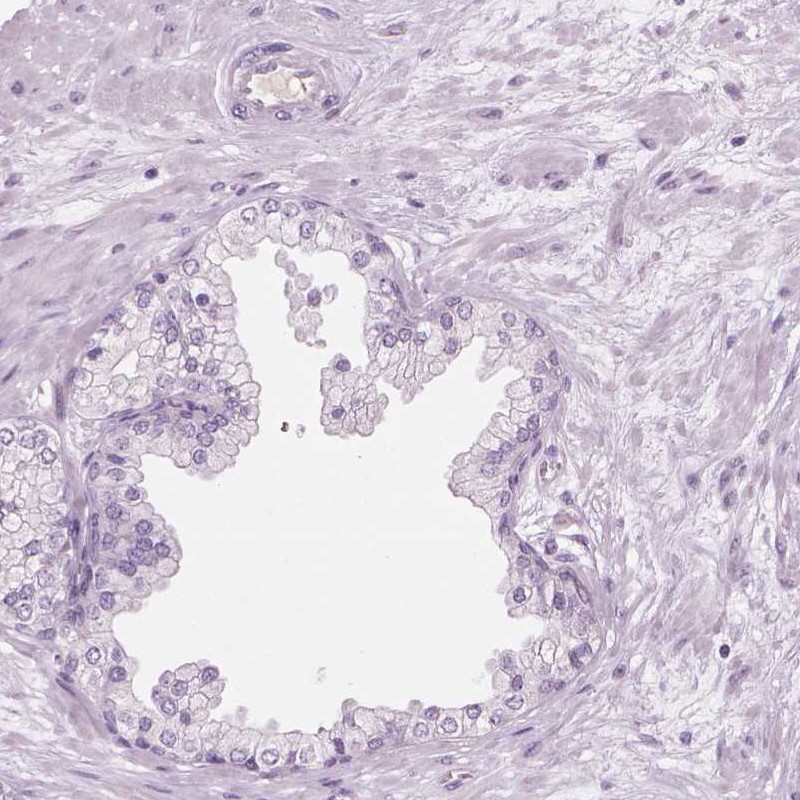

Immunohistochemistry analysis in human fallopian tube and prostate tissues using Anti-CFAP126 antibody. Corresponding CFAP126 RNA-seq data are presented for the same tissues.